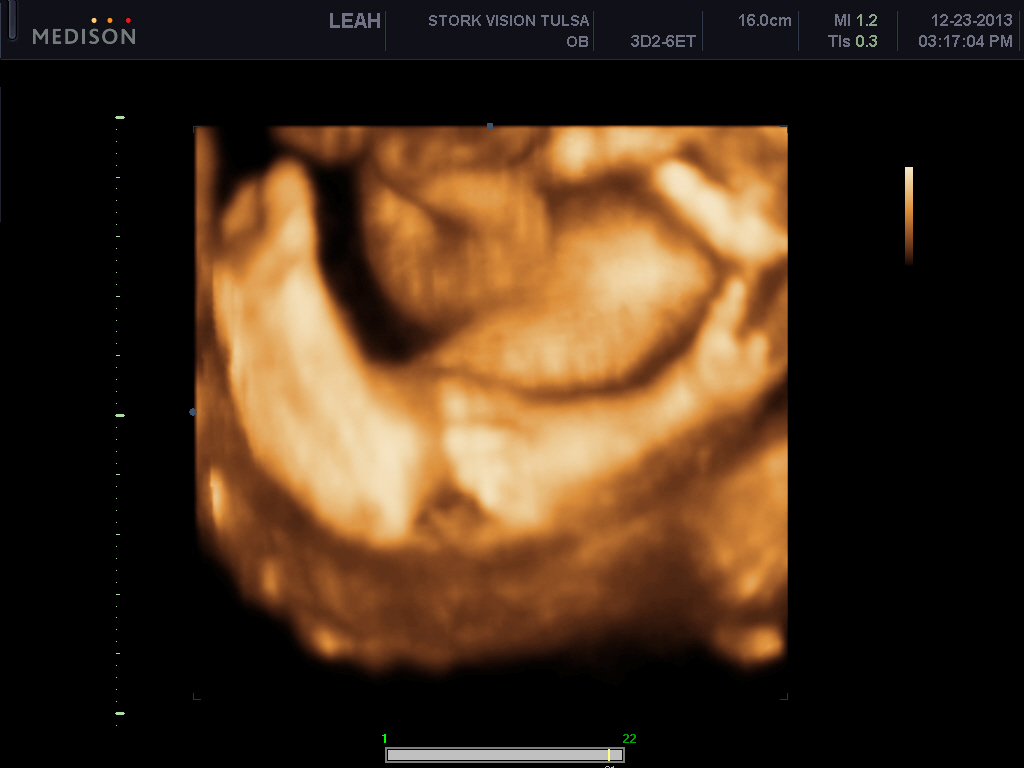

I want to AW my sons 3d ultrasound! :) PIP heavy

He's freaking adorable! These are my favs out of about 70 pictures..

Perfect baby feet